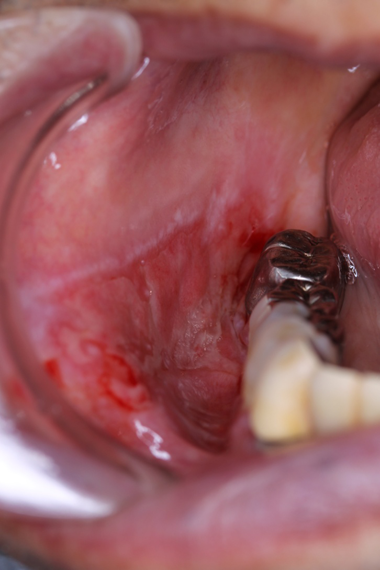

左側頬粘膜扁平苔癬

金属冠と相対する左側頬粘膜に発現した隆起状の扁平苔癬